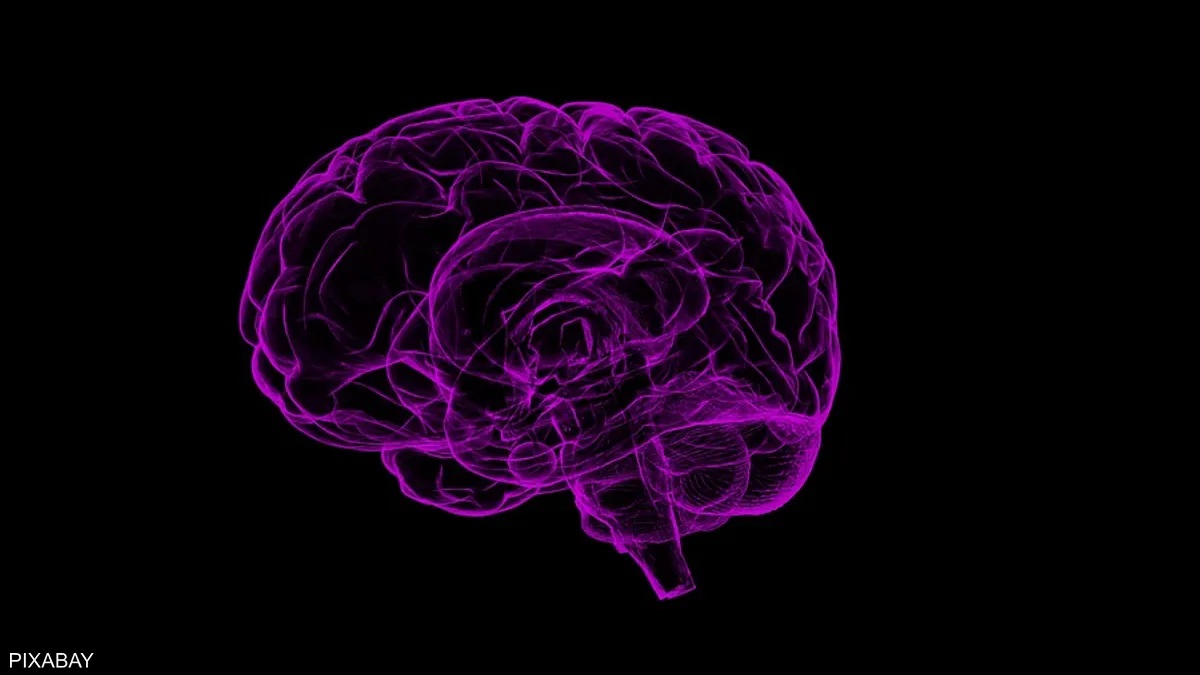

توصلت دراسة طبية حديثة إلى أن العلاج التعويضي بالهرمونات يمكن أن يمنع مرض الزهايمر لدى النساء المعرضات لخطر الإصابة أكثر من غيرهن.

وبحسب شبكة “سكاي نيوز” البريطانية، قال الباحثون إن العلاج بالهرمونات البديلة أو المعروف باسم “إتش آر تي”، يرتبط بذاكرة أفضل ووظيفة معرفية وحجم أكبر للدماغ في وقت لاحق من الحياة لدى النساء اللاتي يحملن جينا يعتبر أقوى عامل خطر للإصابة بمرض الزهايمر.

ويعد الجين”APOE4” أقوى عامل خطورة للإصابة بالمرض، على الرغم من أن وراثته لا تعني أن الشخص سيصاب بالتأكيد بهذه الحالة.

وقالت البروفيسور آن ماري مينيهان، من كلية الطب بجامعة “إيست أنجليا: “نحن نعلم أن 25 بالمئة من النساء في المملكة المتحدة يحملن جين APOE4 وأن ما يقرب من ثلثي مرضى الزهايمر من النساء”.

وأضافت: “يُعتقد أن السبب وراء ارتفاع معدلات انتشار المرض بين الإناث مرتبط بآثار انقطاع الطمث، وتأثير عامل الخطر الوراثي APOE4 الذي يكون أكبر لدى النساء”.

وأكملت: “أردنا معرفة ما إذا كان العلاج التعويضي بالهرمونات يمكن أن يمنع التدهور المعرفي في ناقلات APOE4 التي ترفع نسب الخطر”.

وأظهرت نتائج الخبراء أن حاملي الجين APOE4 الذين استخدموا العلاج التعويضي بالهرمونات لديهم إدراك أفضل وأحجام دماغية أعلى من أولئك الذين لا يستخدمونه.